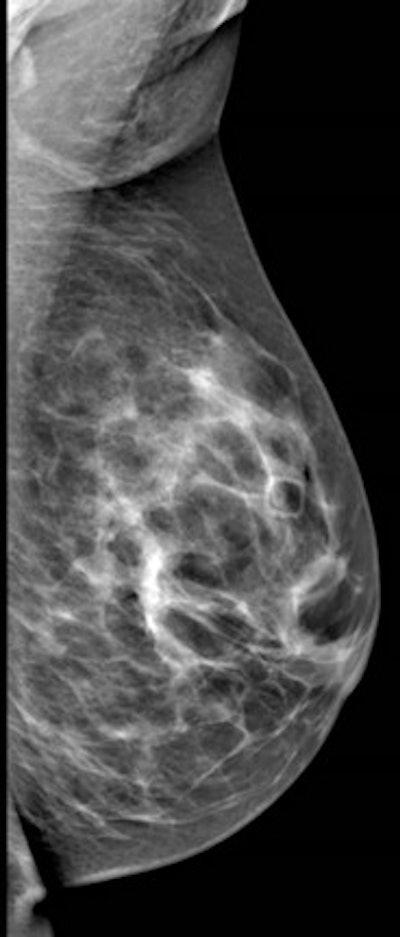

Left mediolateral oblique (left image) and left cranial-caudal (right image) unilateral diagnostic mammogram for a 42-year-old women presenting with new palpable lump in the left upper central breast with no suspicious finding on mammogram. All images courtesy of Dr. Rola Shaheen, originally appearing in the 2014 show Issue of Arab Health magazine.